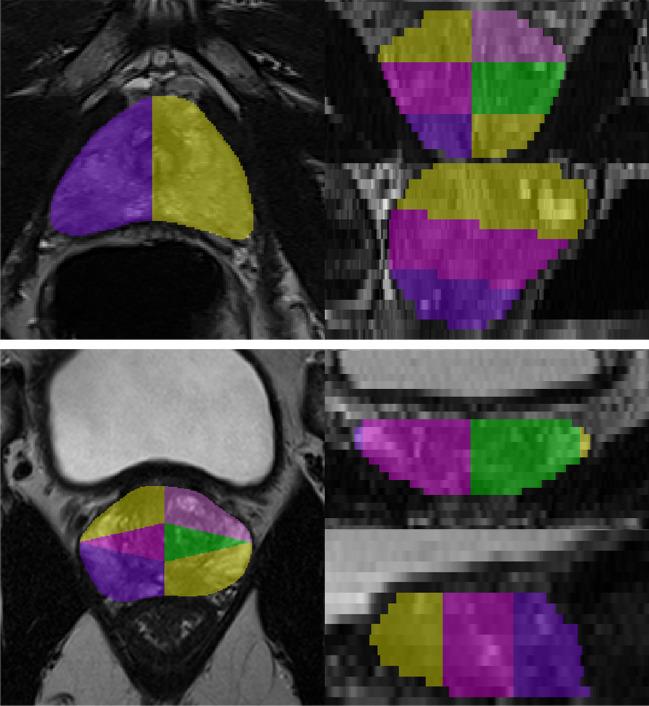

To evaluate a fully automatic deep learning system to detect and segment clinically significant prostate cancer (csPCa) on same-vendor prostate MRI from two different institutions not contributing to training of the system.

In this retrospective study, a previously bi-institutionally validated deep learning system (UNETM) was applied to bi-parametric prostate MRI data from one external institution (A), a PI-RADS distribution-matched internal cohort (B), and a csPCa stratified subset of single-institution external public challenge data (C). csPCa was defined as ISUP Grade Group ≥ 2 determined from combined targeted and extended systematic MRI/transrectal US-fusion biopsy. Performance of UNETM was evaluated by comparing ROC AUC and specificity at typical PI-RADS sensitivity levels. Lesion-level analysis between UNETM segmentations and radiologist-delineated segmentations was performed using Dice coefficient, free-response operating characteristic (FROC), and weighted alternative (waFROC). The influence of using different diffusion sequences was analyzed in cohort A.

In 250/250/140 exams in cohorts A/B/C, differences in ROC AUC were insignificant with 0.80 (95% CI: 0.74-0.85)/0.87 (95% CI: 0.83-0.92)/0.82 (95% CI: 0.75-0.89). At sensitivities of 95% and 90%, UNETM achieved specificity of 30%/50% in A, 44%/71% in B, and 43%/49% in C, respectively. Dice coefficient of UNETM and radiologist-delineated lesions was 0.36 in A and 0.49 in B. The waFROC AUC was 0.67 (95% CI: 0.60-0.83) in A and 0.7 (95% CI: 0.64-0.78) in B. UNETM performed marginally better on readout-segmented than on single-shot echo-planar-imaging.